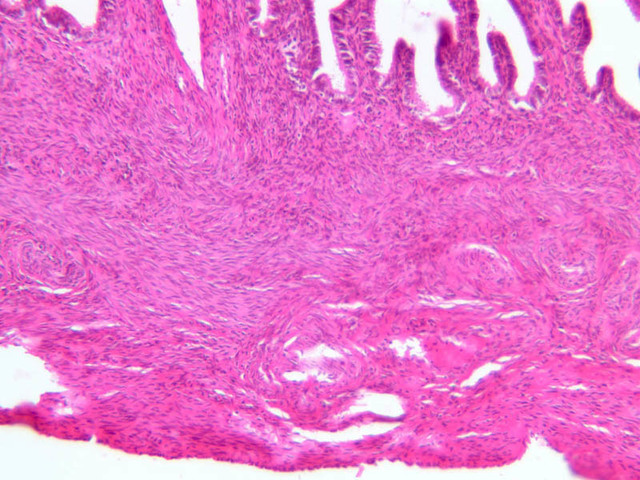

Secretory Phase

This phase occurs on days 15 to 27 and corresponds to the ovarian luteal phase characterized by rising levels of progesterone. The epithelial cells begin to secrete a mucoid fluid rich in nutrients, especially glycogen. The glands become highly coiled and folded and toward the end, very distended. The density of the stroma lessens as it becomes edematous. (slides B-99 [2.5x, 10x, 20x, 40x] [2.5x, 10x, 20x, 40x]; B-100 [1x, 2.5x] [2.5x, 10x, 20x, 40x] [2.5x, 10x, 20x, 40x])

Uterine Cervix

The endometrium of the cervical canal does not slough during the menstrual phase. The glands in this region are relatively large and extensively branched. They are lined by a tall simple columnar epithelium very active in the secretion of mucus. Occasionally these glands become blocked forming Nabothian cysts. The transition of the epithelium of the cervix to that of the vagina is abrupt and is in the region of the external os. At this point, the cervical simple columnar is replaced by the vaginal stratified squamous epithelium (slide B-98 [2.5x-labeled, 10x, 20x, 40x] [2.5x, 10x, 20x, 40x]). This is an area which is commonly inflamed as well as a primary location of cervical cancer.